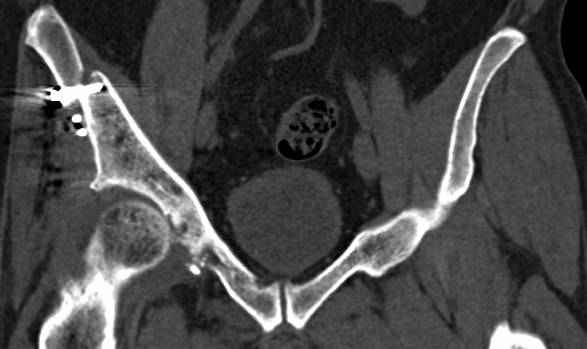

высылаю дополнительно сканы.

итак, второй вариант: высокий двухколонный с вовлечением КПС... Ни одно из основных повреждений не репонировано, кроме задней стенки. Скорее всего попытка реконструкции вертлуги сейчас будет очень травматичной и не очень эфективной, т.е. вероятный риск более значим, чем ожидаемая польза... Лучше подождать, и потом сразу эндопротез